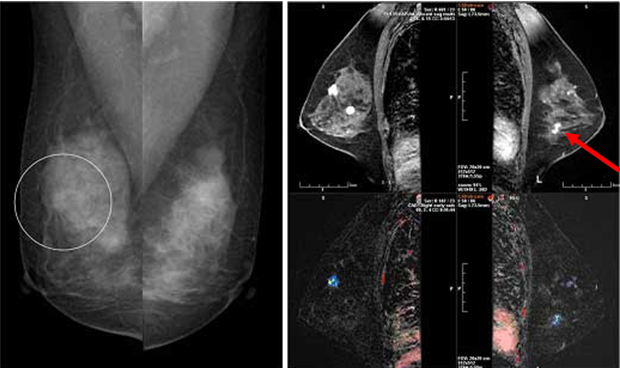

유방암은 유방의 양성 종양이 아니라 유방 밖으로 퍼져 생명에 영향을 미치는 악성 종양입니다. 이전에는 유방암이 동양인 여성에서 매우 드물었지만 최근에는 서양식 생활양식이 대중화되면서 발병률이 급격히 증가하고 있습니다. 유방암은 조기에 치료하면 치료가 쉽기 때문에 유방암의 초기 증상을 아는 것이 중요합니다. 그래서 이번 글에서는 유방암 초기 증상과 유방암 자가진단법에 대해 알아보겠습니다.

유방암 초기 증상

✔유방암 초기 증상 - 유방 결절 및 덩어리

유방에 있는 2cm 길이의 덩어리를 결절이라고 하고 이 크기보다 큰 것을 덩어리라고 합니다. 덩어리는 가장 흔한 증상으로 유방암 증상의 약 70%를 차지합니다. 흔히 유방 덩어리를 만질 때 통증이 없다고 생각하는데 이는 잘못된 것입니다. 대부분의 덩어리는 통증이 없으므로 젊은 여성이 자가 검진을 통해 덩어리를 느끼면 암이라고 생각하고 병원에 가는 것이 좋습니다. 20대의 경우 유방암 발병률은 2.2%입니다.